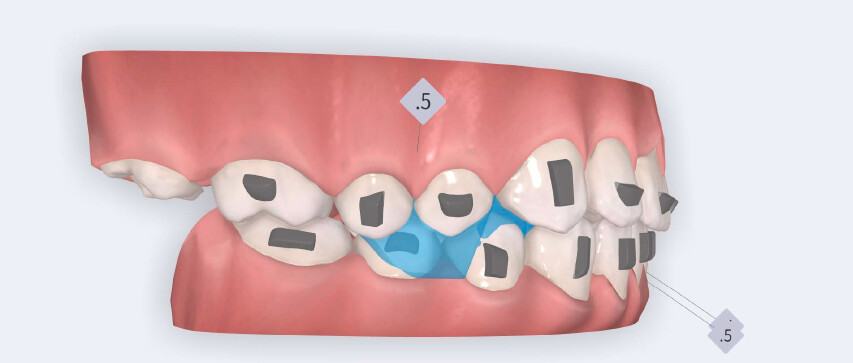

The treatment followed the Angel Aligner A6 mandibular advancement protocol, with the primary objective of achieving early correction of the sagittal discrepancy while simultaneously addressing dental alignment and transverse coordination.

• Initiation of mandibular advancement from the 4th aligner using mandibular advancement blocks;

• Use of Class II elastics on Angel Buttons during the refinement phase to reinforce sagittal mechanics, introduced during the additional aligners stage.

The treatment was carried out using Angel Aligner clear aligners, with strict adherence to periodontal biological limits. Both maxillary incisor intrusion and transverse expansion were carefully monitored throughout the process to prevent any periodontal compromise. Mandibular advancement was initiated directly from the 4th aligner using advancement blocks, eliminating the need for a preliminary pre-advancement phase. The patient was at the CS3 stage of cervical vertebral maturation, corresponding to the pubertal growth spurt, a biologically favorable period for condylar remodeling and skeletal adaptation. A total of 35 aligners with advancement blocks were used, followed by 10 additional aligners incorporating Class II elastics on Angel Buttons to finalize rotations and alignment. With weekly aligner changes, the overall treatment duration was approximately 45 weeks (10 months), aligning with the expected biological timeline for condylar remodeling. For mandibular anterior intrusion, the Frog Protocol combined with interproximal reduction (IPR) achieved complete leveling of the Curve of Spee.